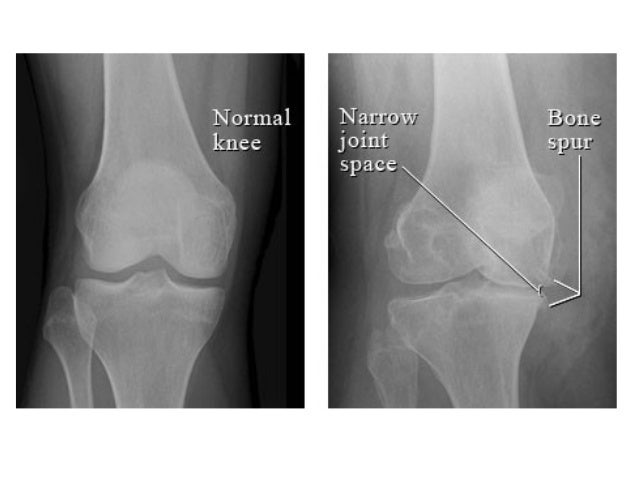

Bone spurs, or osteophytes, are bony growths that form in your joints or in the spine.

They develop over time in patients with arthritis or joint damage. Surgery for arthritis in the fingers varies based on the location of the arthritis. Osteophytes are typically found at the edge of a bone at a joint.

Osteophytes tend to form when the joints have osteoarthritis is most common in the knees, hips, spine and small joints of the hands and base of the. One surgical option is when the larger two joints in the finger, between the proximal phalanx and the middle phalanx (illustrated on this page). Bone spurs can form on many parts of your body, including your Your finger joint pain is probably caused by arthritis.